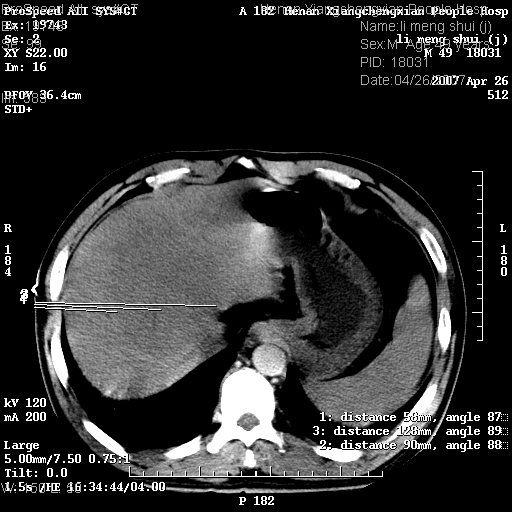

| 患者,男,49岁, 腹疼伴恶心\\呕吐20天,20天前无明显诱因出现右上腹部疼痛,钝疼,无放射,伴恶心\\呕吐,不伴发热.患者不愿增强. b超:肝脏右叶实性占位. ct:肝脏右叶可见一巨块状圆形低密度影,大小约93mm*84mm,其内可见点状高密度影,胆囊、胰腺、脾脏大小、形态及密度未见异常,腹膜后间隙未见肿大淋巴结影。 印象:肝脏右叶巨大肿块,性质待定,建议增强并穿刺活检进一步确诊。 ct平扫: ![]() ![]() ![]() ![]() ![]() ![]() ![]() ![]() ![]() ![]() ![]() ![]() ![]() ![]() ![]() ![]() ![]() 肝脏右叶肿块ct引导下穿刺活检术 患者于16时05分仰卧于ct检查台上,首先行肝脏ct扫描确定进针位置、深度、角度。在局麻下行ct引导下肝脏右叶肿块穿刺活检术。常规消毒、铺巾、局麻。在ct引导下使活检针经右侧腋中线、第9肋间隙垂直胸壁进针90mm,针头进入病变预定位置。在病变预定位置多点、多方向抽取小米样病变组织多块,涂片五张送病理检查。术后穿刺点局部无出血,未出现腹腔积液等并发症。术中及术后患者生命体征稳定,手术于17时10分成功完成。患者安返病房。 穿刺片 ![]() ![]() ![]() ![]() ![]() ![]() ![]() ![]() ![]() ![]() ![]() ![]() ![]() ![]() ![]() ![]() 病理结果肝细胞癌 ![]() 原贴地址:http://www.radinet.com.cn/forum_view.asp?forum_id=4&view_id=24130 ok |